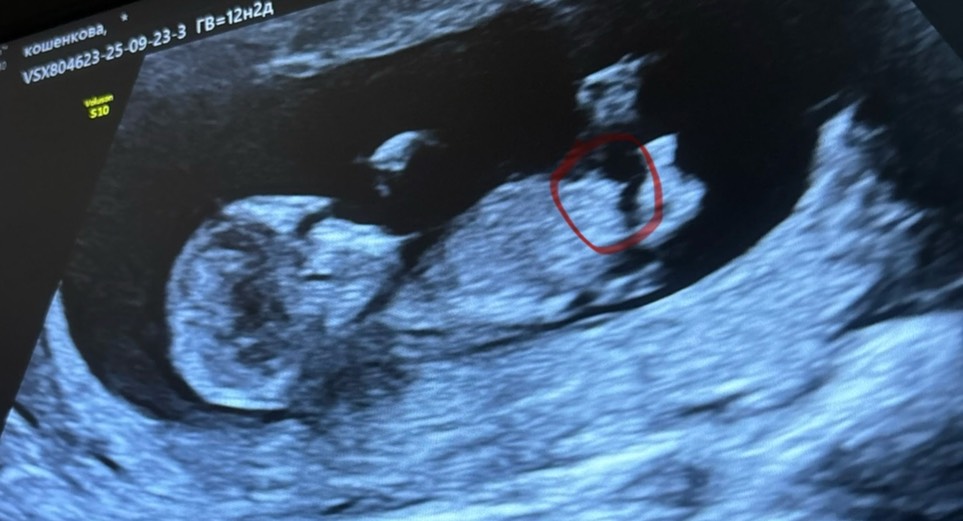

Мальчик или девочка )? Как думаете на снимке узи мальчик или девочка ? То что торчит это пуповина или половой бугорок 🙈? Погадаем ) 😅срок 12.1

Хотелось бы вам пожелать девочку, но кажется мальчик.. Ждите 20 неделю или анализ крови на y хромосому